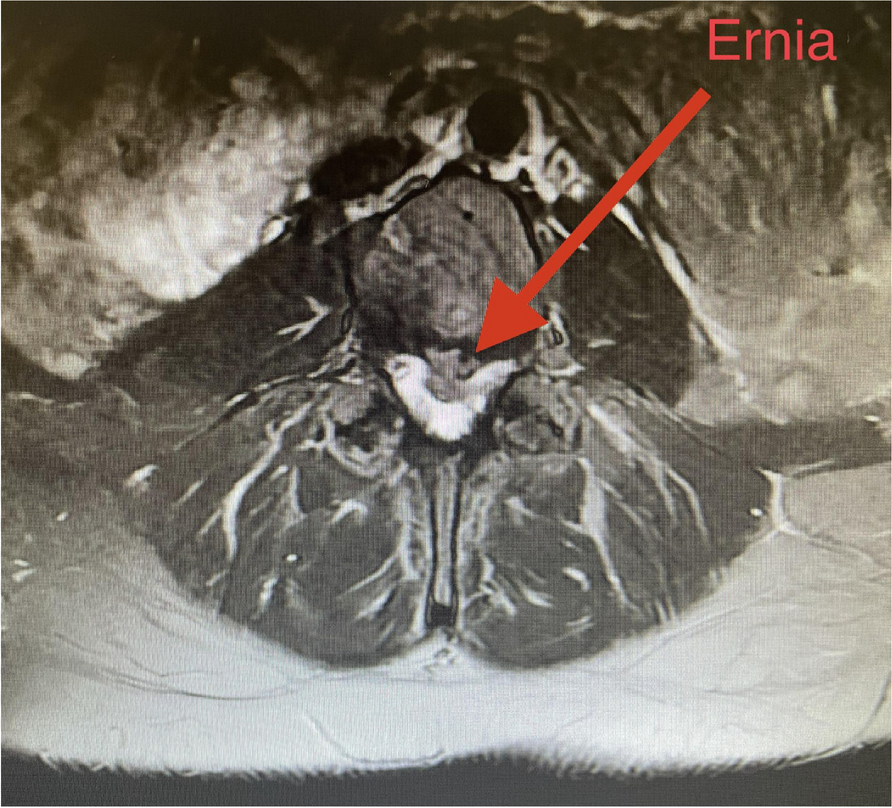

A few hours after the admission in ICU he reported a blunt abdominal pain, mainly on the right side, nausea and the exams showed increased amylase levels, urologists excluded any surgical involvement of pancreatic tissue and suspected a transient sphincter of Oddi dysfunction [3]. After one night in ICU he was transferred to the urology ward due to his clinical stability, even though Amylase peaked at 2340 U/l. Two days later abdominal pain increased to severe, with characteristics of peritonism and increased inflammatory markers. An abdomen-thorax CT scan revealed acute pancreatitis (AP) (Figure 1) and he was transferred to ICU. He started a standard treatment for acute pancreatitis and antibiotic therapy [4].

On postoperative day nine, due to general deterioration of clinical conditions and further anemization that required blood transfusion, he underwent an emergency laparotomy, in which propofol was not used as an anesthetic drug, that found a completely necrotic pancreas. The following day he faced a multi organ failure (MOF) which rapidly led to death. Consent to publish the case report was accorded by the family.

Acute pancreatitis (AP) Is a complex and severe disease with a high mortality rate [4]. Propofol, is a common anesthetic drug which is widely used in daily practice for sedations and general anesthesia [5], few cases of Propofol Induced AP have been published, in which the diagnosis has been made excluding more common causes [6].

In fact, Propofol is listed as a possible cause of AP, class Ib, based on the classification of Badalov et al. [7]. Following the scheme proposed by the systematic review by Haffar et al for Propofol induced AP [6] we could confirm that our hypothesis is plausible. He satisfied the American College of Gastroenterology criteria for AP [8,9] and it is classified as severe acute pancreatitis according to the Revised Atlanta Classification with peripancreatic necrotic fluid collection [10]. Marshall score [11] after admission was two and Naranjo et al [12] probability scale for drug adverse reaction was three, meaning that the adverse reaction is possible. Latence according to Badalov et al [7] has been short or intermediate. Exclusion of other plausible causes, timing of pancreatitis symptoms and previous cases in literature support our hypothesis of propofol induced pancreatitis.

Fig. 1 (abstract A21).

See text for description